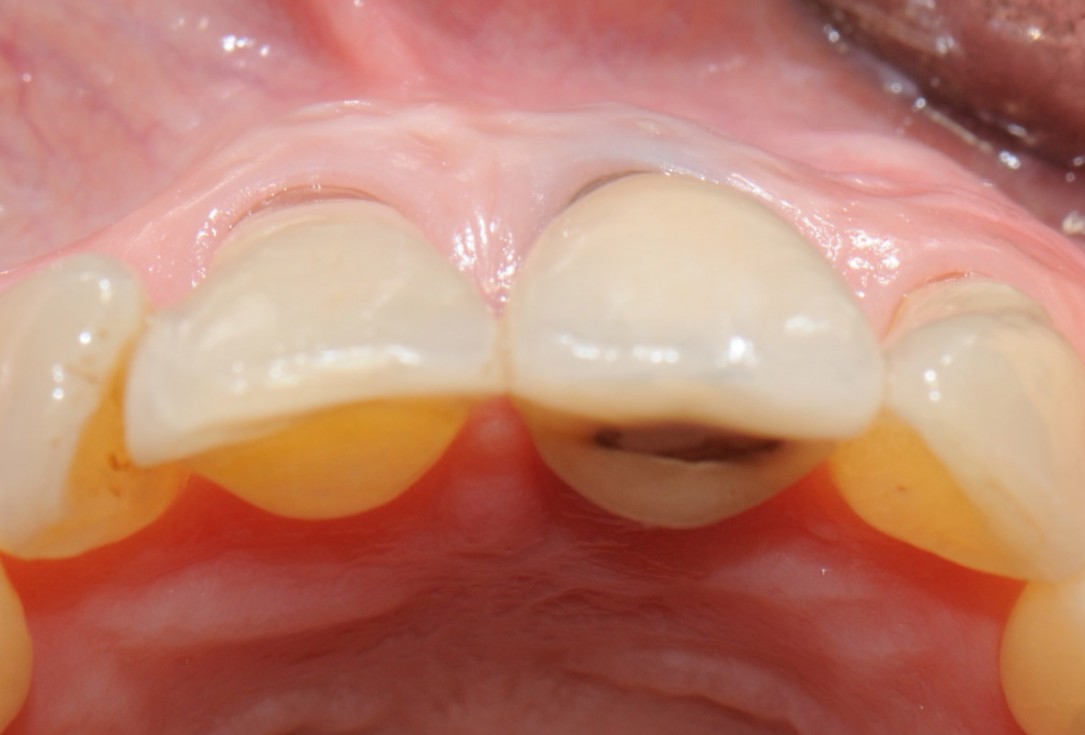

2/18 - Occlusal view showing buccal bone lossTooth extraction and socket sealing with mucoderm® - Dr. A. Rossi